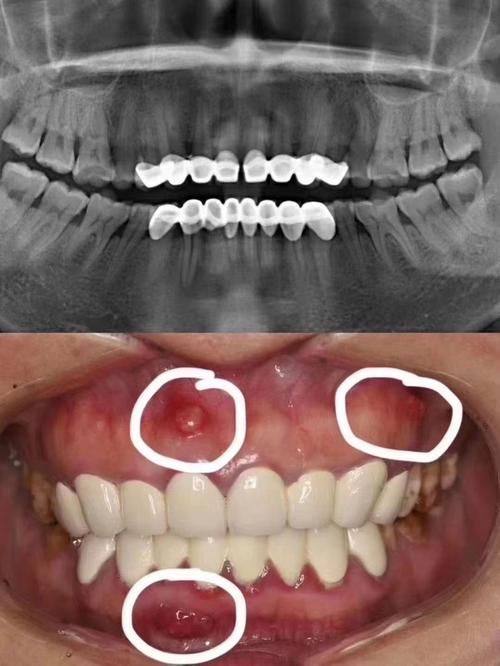

牙齿种植:依托专精医生团队与精良设备,可开展多种种植修复方案,适配不同缺牙需求,帮助患者修复正常咀嚼功能与美观外观。

根管治疗:针对牙髓感染等问题进行专精治疗,保留患牙避免拔除。